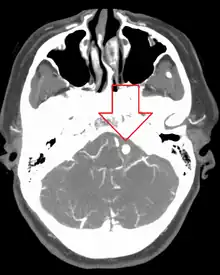

![]() | |

| Angiography of an aneurysm in a brain artery. The aneurysm is the large bulge in the center of the image. | |